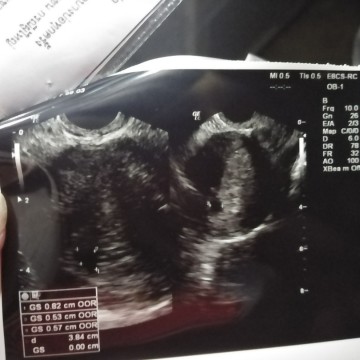

เจอแต่ถุงตั้งครรภ์แต่ยังไม่เจอเด็ก

สอบถามหน่อยค่ะ พอดีเราไปซาวมา ปกติถ้านับจากประจำเดือนครั้งสุดท้ายแล้วอายุครรภ์ก็จะประมาณ7สัปดาห์ค่ะ แต่คุณหมอซาวบอกเห็นแต่ถุงตั้งครรภ์เล็กๆ ในการซาวอายุครรภ์เพิ่งจะได้5วีคเองค่ะ มันเลยยังไม่เห็นอะไร หมอเลยนัดตรวจใหม่อีก ทีอีก2สัปดาห์ เราเคยท้องลมไปแล้ว เรากังวลที่จะเป็นอีกมีแม่ๆท่านไหนเคยเจอเหตุการณ์แบบนี้บ้างมั้ยค่ะ